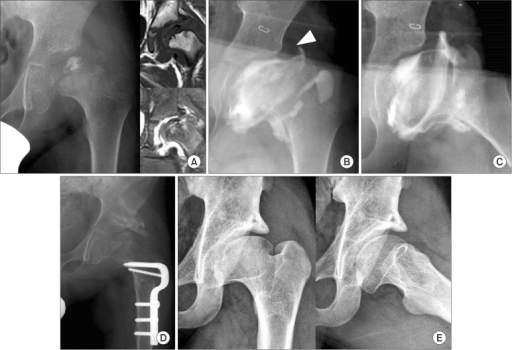

AP pelvis radiograph demonstrating left hip Legg-Calvé-Perthes disease in the fragmentation stage. There is increased radiodensity, flattening, and fragmentation of the femoral epiphysis. The lateral pillar height is reduced to approximately 40% (Herring Group C). Note the 'head at risk' signs: lateral subluxation with break in Shenton's line and horizontal physis. The contralateral hip is normal for comparison.

Source: Combined Shelf Acetabuloplasty with Femoral Varus Osteotomy in Severe Legg-Calve-Perthes Disease • PMC4667119 • CC-BY